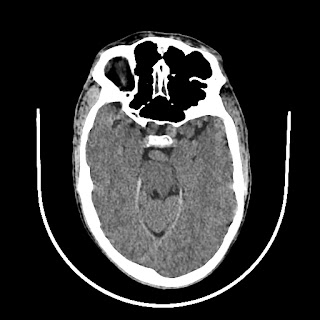

CT scan of brain images: